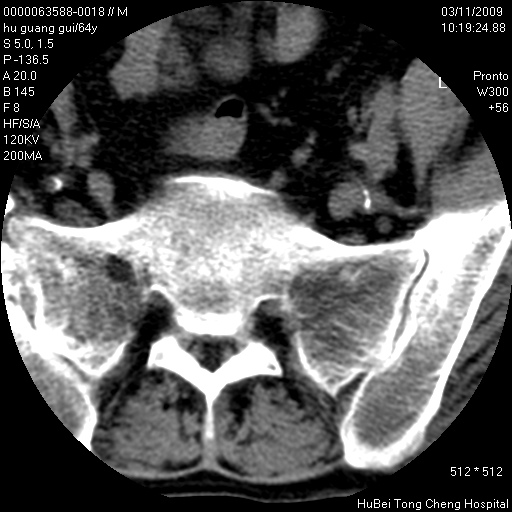

患者 男,64岁。腰痛十余天。(临床未提供其他病史)

临床诊断:腰痛原因待查(腰椎间盘突出症?)。

腰椎间盘ct轴位平扫(层厚5mm,层距4mm),图像如下:

腰椎退行性变,腰4—5椎间盘膨出。

右侧骶骨侧块骨侵蚀,骶髂关节骨性关节面破坏,并见软组织肿块,考虑骨转移瘤可能,进一步检查。

1.腰椎退行性变,腰4—5椎间盘膨出。

2.右侧骶骨侧块骨侵蚀,骶髂关节骨性关节面破坏,并见软组织肿块,考虑:脊索瘤,骨转移瘤可能,进一步检查。

1)腰椎退行性变,l4—5椎间盘膨出。2)骶骨右侧块骨转移瘤可能,3)水平骶椎。建议作一步检查。